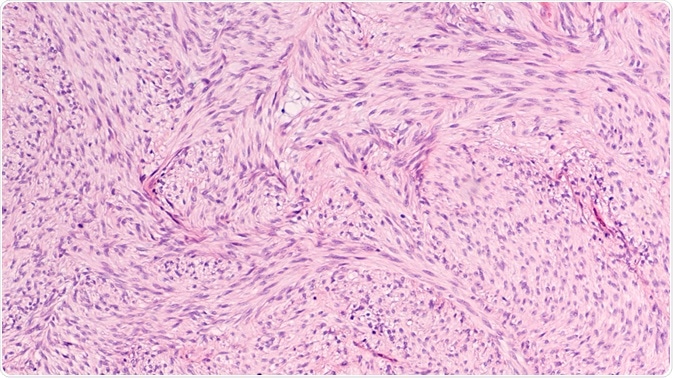

Stroma is the region of an organ or tissue that has a connective or structural role and is also comprised of all of the constituents that do not have a specific function within the organ, such as blood vessels, connective tissue, ducts, and nerves.

Connective tissues can be found within the stroma, with this essential tissue belonging to a group called: connective tissue proper.

The main function of this connective tissue proper is to fully secure the parenchymal tissue into place, which includes the nerves and blood vessels, to spread mechanical tension as to reduce any localized physical stress, and to bind the organs together. The stromal tissue mainly consists of an extracellular matrix that contains cells of connective tissue.